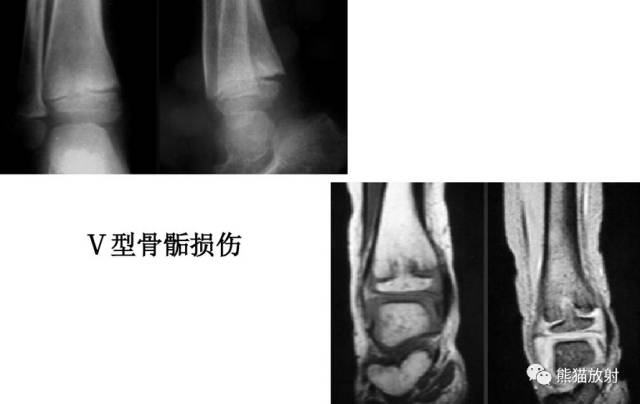

V型:骺板挤压性损伤(少见,多在晚期发生生长障碍时才能作出诊断)

Salter-Harris V型:由轴向压力导致的挤压伤,表现为骺板的明显扭曲或变窄。

第五型(V型) 骺板挤压性损伤,少见,占骨骺损伤的1%。由于严重暴力损伤造成,相当于骺板软骨的压缩骨折,有学者指出此型损伤只发生在一个方向活动的关节,如膝关节和踝关节。由于软骨细胞严重损伤破坏或来自骨骺营养血管广泛损伤,导致骺板早闭和生长停止。逐渐出现骨骼变形和关节畸形 ,但早期X线表现常常为阴性结果,多在晚期发生生长障碍时才能作出诊断。